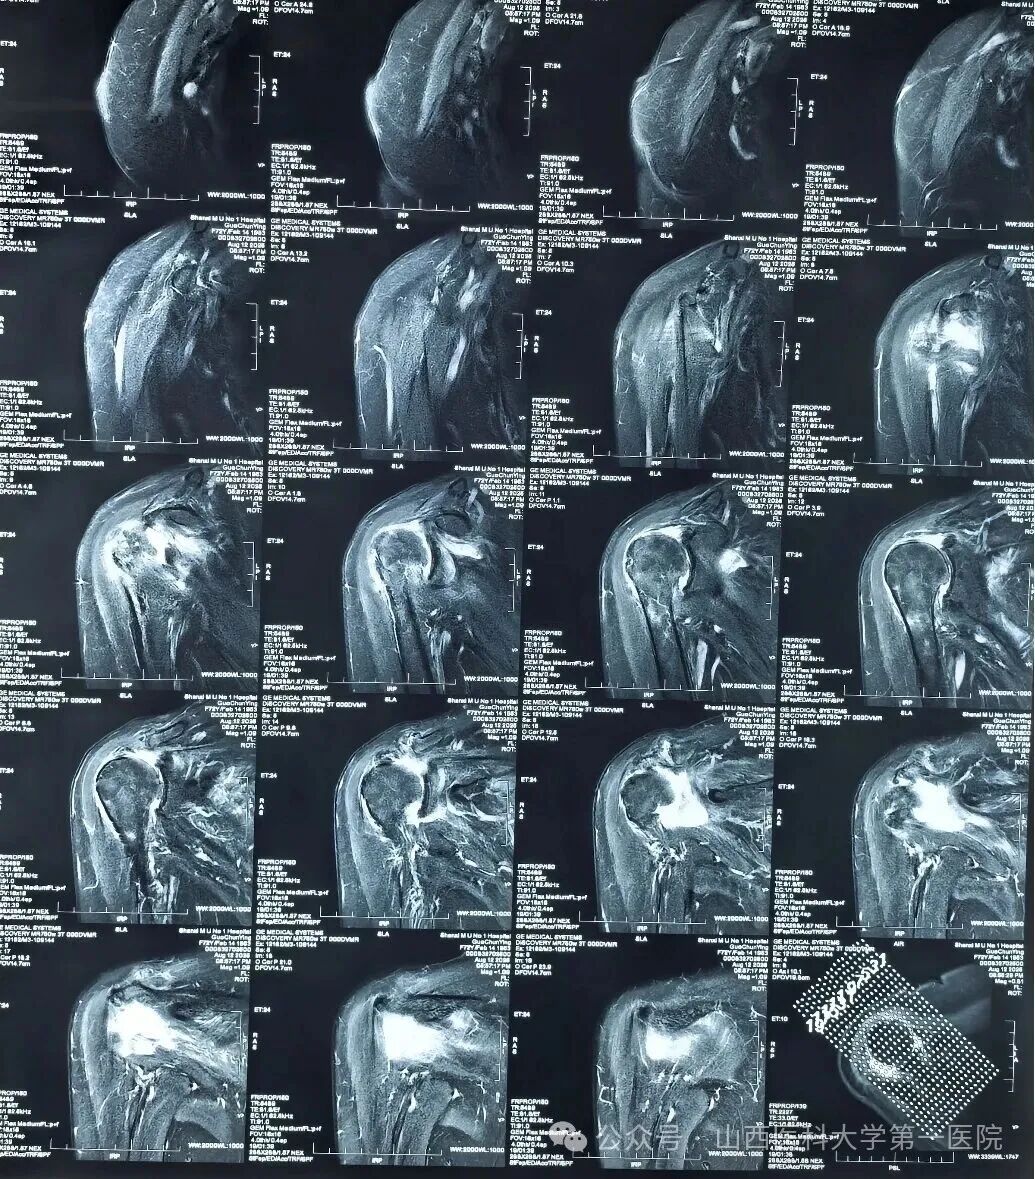

并完善右肩MRI提示右肩巨大肩袖撕裂。针对郭女士的病情结合查体,杨自权团队诊断为“不可修复的右侧巨大肩袖撕裂”,在详细向患者及家属说明病情并介绍治疗方案后,郭女士及其家属选择行“微创可吸收球囊植入术”进行治疗。

术前右肩MRI显示巨大间隙撕裂